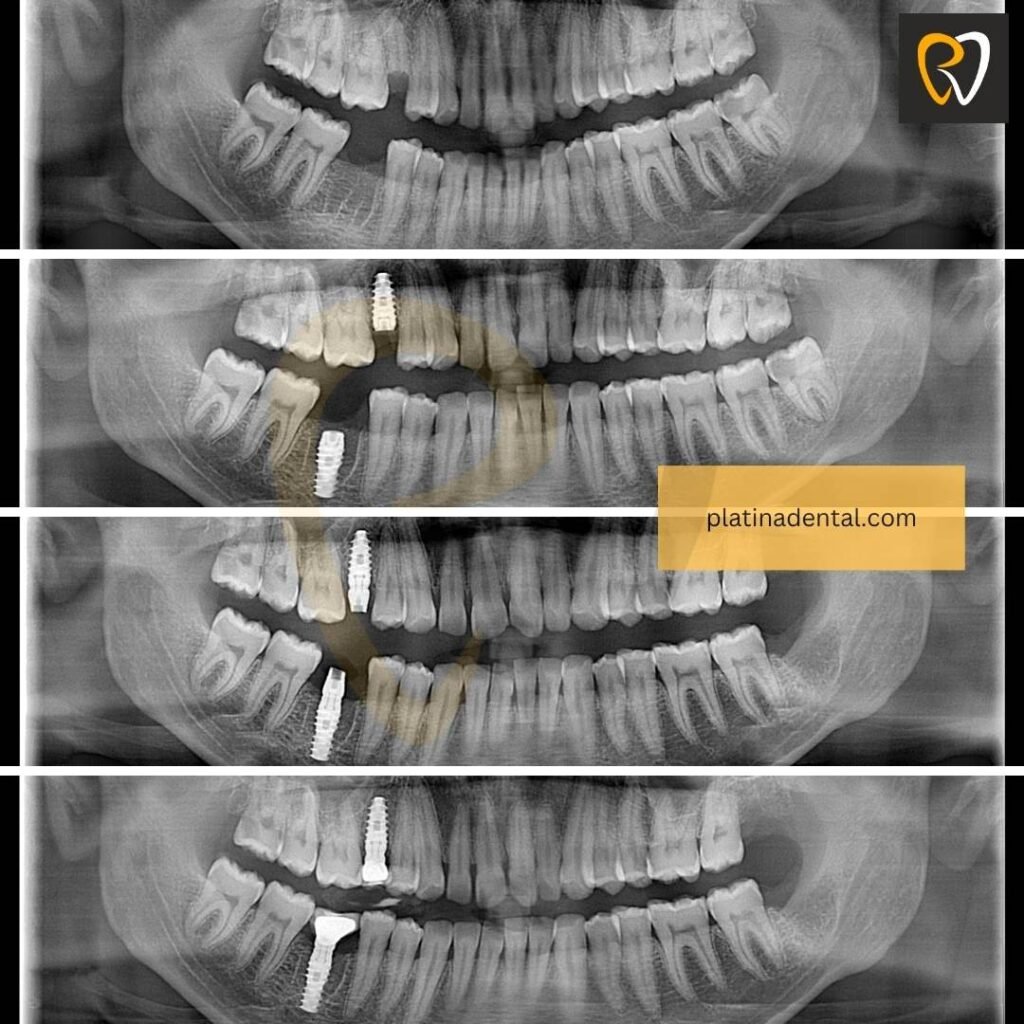

Single Tooth Implant Transformation

Patients who replace one missing tooth often notice:

- Improved smile symmetry

- Better chewing comfort

- No visible difference from natural teeth

Immediate Implant Transformation

Immediate implant cases show:

- Faster aesthetic recovery

- Reduced waiting time

- Natural gum contour preservation